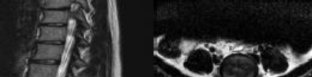

CLINICAL SITUATION

Figures 1 and 2 are the sagittal and axial MRI images at the L4-5 level from a patient with intractable left leg pain, paresthesias, and weakness of grade 3

of 5. Physical therapy has failed, and the patient feels he is becoming progressively weaker.

Which nerve root is being affected?

Discussion: C

The MRI images show a left L4-5 posterolateral disk herniation compressing the left L5 nerve root. Posterolateral disk herniations in the lumbar spine affect the traversing nerve roots; therefore, at the L4-5 level, the traversing L5 nerve would be affected. Far-lateral disk herniations in the lumbar spine affect the exiting nerve roots, so a far-lateral herniation at L5-S1 would affect the L5 nerve root also. The motor innervation for the lumbar nerve roots are L2: hip flexion, L3: knee extension, L4: ankle dorsiflexion, L5: long toe extension, and S1: ankle plantar flexion. The sensory innervation for the lumbar nerve roots are L3: medial thigh, L4: anterolateral thigh and medial calf, L5: anterolateral calf, and S1: lateral foot. Nonsurgical treatment, including medications and physical therapy, has failed, and the patient has noticed a progressive deficit confirmed by weakness of grade 3 of 5 on examination. Surgery is indicated because of the patient’s progressive weakness and the failure of nonsurgical care. A fusion is not indicated without evidence of instability.

Question 45 of 100

Figures 1 and 2 are the sagittal and axial MRI images at the L4-5 level from a patient with intractable left leg pain, paresthesias, and weakness of grade 3 of 5. Physical therapy has failed, and the patient feels he is becoming progressively weaker.

What other disk herniation location also could affect the same nerve root?

4. Posterolateral L5-S1 Discussion: B